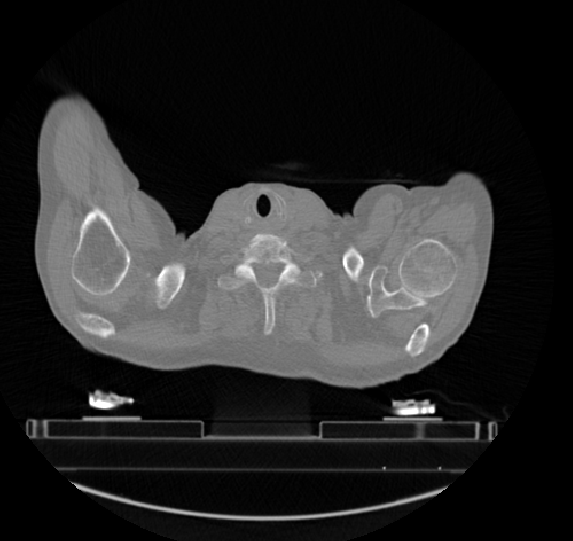

2.2 形态学特征(Form Factor Features) 本类特征主要通过数学的方法刻画病灶部位的形状,试图描述病灶部位的形状、紧致性等信息。图3.a和图3.b分别表示形态不同的两个三维病灶。假设考虑对这两个三维病灶求形态学特征,将有如下情况:

a b 图3. 不同形态的两个三维病症

VolumeCC:体积,描述病灶体积大小,若体积越大,则VolumeCC越大; Surface:表面积,描述病灶表面积大小,若表面积越大,则Surface越大; SurfaceVolumeRation:表面积体积比,描述病灶表面积与体积之比,如果三维病灶的边缘不规则程度越大,则该比值越大,说明三维肿瘤的异质性越大;假设图3.a病灶的边缘不规则程度小于图3.b,则表面积体积比可表述为SurfaceVolumeRatio& #40;3.a& #41;< SurfaceVolumeRatio & #40;3.b& #41;; Compactness:紧致性,描述了病灶的球状性程度;若病灶越像球形,则Compactness值越大;假设图3.b病灶较图3.a病灶更接近于球形,则可表述为 Compactness& #40;3.a& #41;< Compactness& #40;3.b& #41;; Maxmun3DDiameter:最大直径,描述三维病灶部位的最长直径,病灶部位的跨度越大,则Maxmun3DDiameter值越大。